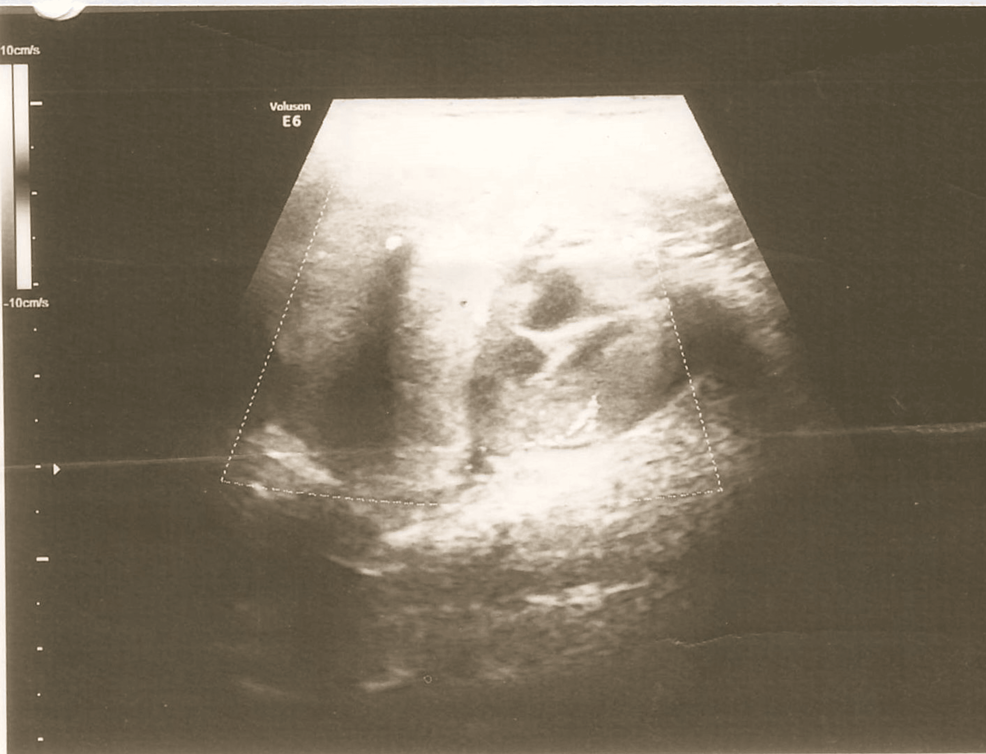

On local examination, there was a single firm mobile swelling in the right submandibular region measuring 5*4 cm and was non-tender. All relevant investigations were done and had normal thyroid function studies. Ultrasonography of the right submandibular region showed an enlarged submandibular gland with a hypoechoic lesion and vascularity on Doppler, suggestive of submandibular sialadenitis (Figure 1). FNAC of the swelling was done, and it showed numerous small basaloid cells in singles and multilayered. These cells have round to regular/oval nuclei with bland, granular chromatin. The background shows a few naked nuclei with fibrous scanty chondromyxoid stroma and hyaline material. These features are suggestive of a basaloid neoplasm like basal cell adenoma or pleomorphic adenoma. Contrast-enhanced computed tomography (CECT) of the neck showed a large lobulated mass with irregular margins and cystic areas in the right submandibular region extending up to the midline; post-contrast showed heterogenous enhancement with necrosis and coarse calcific foci within the lesion, suggestive of malignant neoplasm such as adenoid cystic carcinoma with origin from the deep lobe of the submandibular gland (Figure 2). Another small enhancing lesion with coarse calcific foci was seen at the left pharyngeal mucosal space, suggestive of a metastatic lingual lymph node. Also, the thyroid gland was not visualized, and a small oval isodense lesion with homogenous post-contrast enhancement was seen in the left lateral aspect of trachea, in the expected location of thyroid, suggestive of remnant thyroid/congenital hypoplastic thyroid. Thus the patient was advised surgical excision of the swelling.